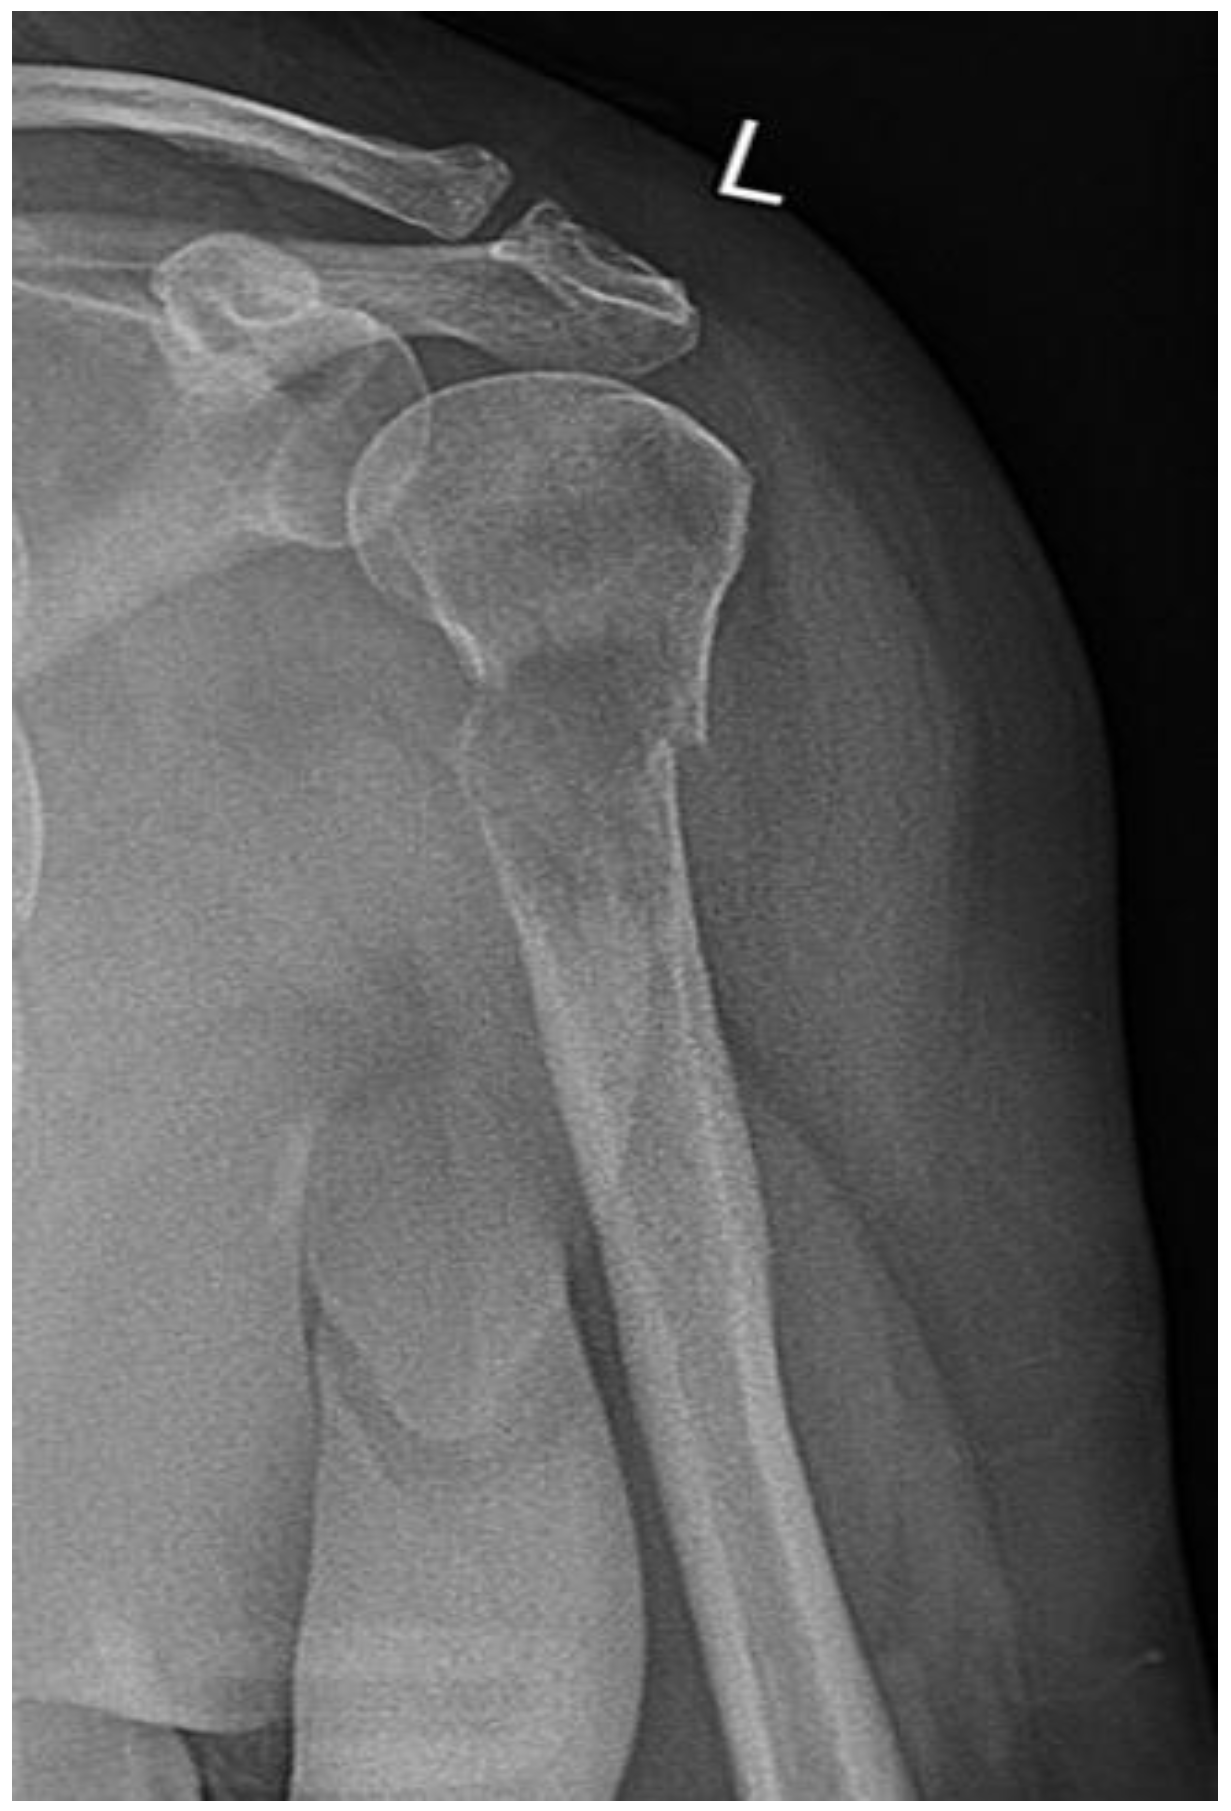

Radiograph of the left arm revealed a pathological humerus fracture (Figure 1).

Figure 1. X-ray of left arm.